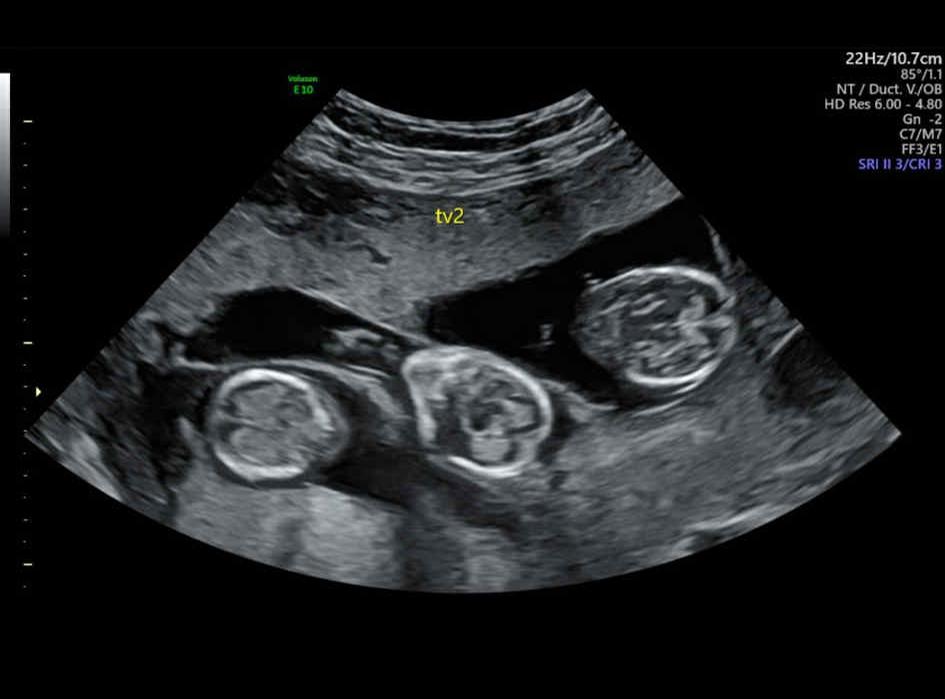

Femeia în vârstă de 50 de ani care a născut tripleți. Cum e posibil și care e explicația medicilor | Imaginea 2 din 8 | Galerie Foto

Chiar dacă medicii i-au dat șanse puține, Marie a reușit să rămână însărcinată cu tripleți. Femeia în vârstă de 50 de ani care a născut tripleți. Cum e posibil și care e explicația medicilor Femeia în vârstă de 50 de ani care a născut tripleți. Cum e posibil și care e explicația medicilor Femeia în vârstă de 50 de ani care a născut tripleți. Cum e posibil și care e explicația medicilor Femeia în vârstă de 50 de ani care a născut tripleți. Cum e posibil și care e explicația medicilor Femeia în vârstă de 50 de ani care a născut tripleți. Cum e posibil și care e explicația medicilor Femeia în vârstă de 50 de ani care a născut tripleți. Cum e posibil și care e explicația medicilor Femeia în vârstă de 50 de ani care a născut tripleți. Cum e posibil și care e explicația medicilor